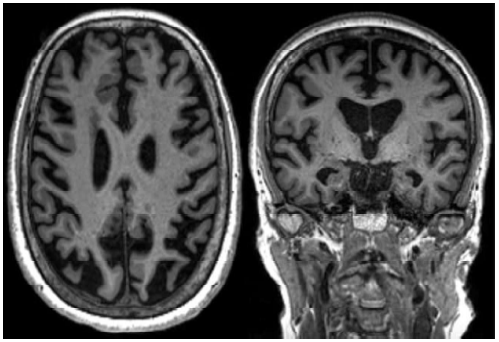

A atrofia da porção mesial do lobo temporal é frequente na Demência por Doença de Alzheimer (DA). A escala analógica visual MTA (mesial temporal atrophy), consegue avaliar a presença da atrofia mesial, e é classificada em números considerando a espessura da fissura coroidea e do corno temporal e a altura do hipocampo, e tem sensibilidade e especificidade de cerca de 85% para o diagnóstico de DA. Analise a imagem de ressonância abaixo.

Pode-se considerar que a imagem da ressonância acima, corresponde a qual número MTA?